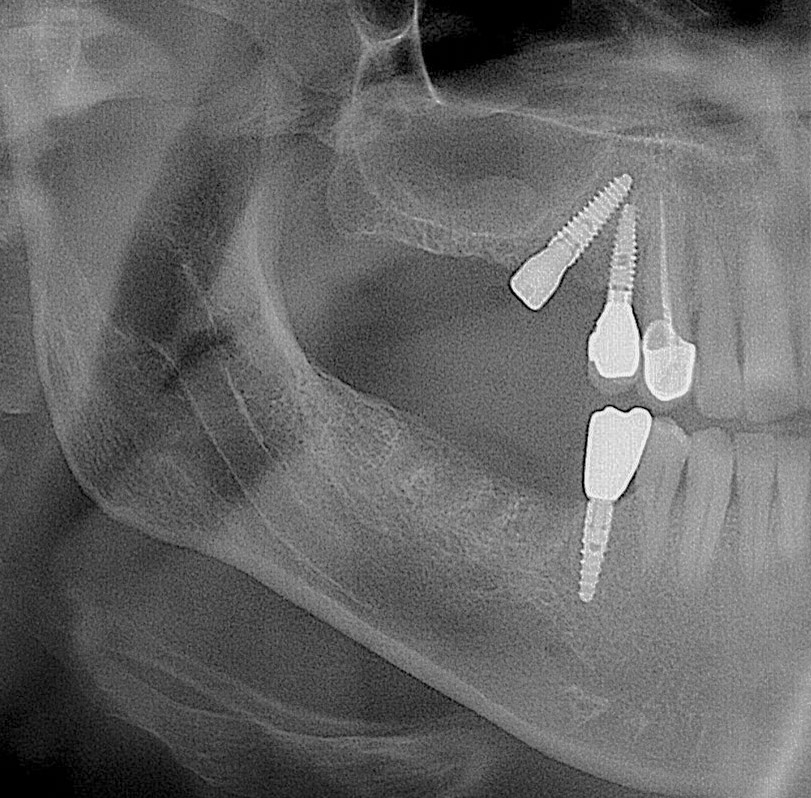

✅ Цифрова диагностика та планування

✅ Атравматичне видалення із збереженням кісткової тканини дуже важливо для майбутньої імплантації

Також дивітьсяімплантація після видалення